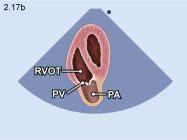

|

|

Cửa sổ siêu âm từ mỏm tim

Mặt cắt 5 buồng Ngả đầu dò hướng chùm siêu âm ra trước để bộc lộ đường ra thất phải, van động mạch phổi và động mạch phổi |

Đường ra thất phải (RVOT) Van động mạch phổi (PV) Động mạch phổi (PA) |

|||||